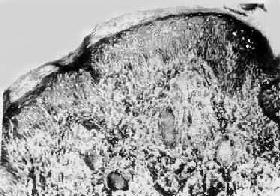

图18-17 结核样型麻风

真皮内有主由类上皮细胞构成的结节状病灶,其中可见Langhans细胞,颇似结核结节,但中央无干酪样坏死